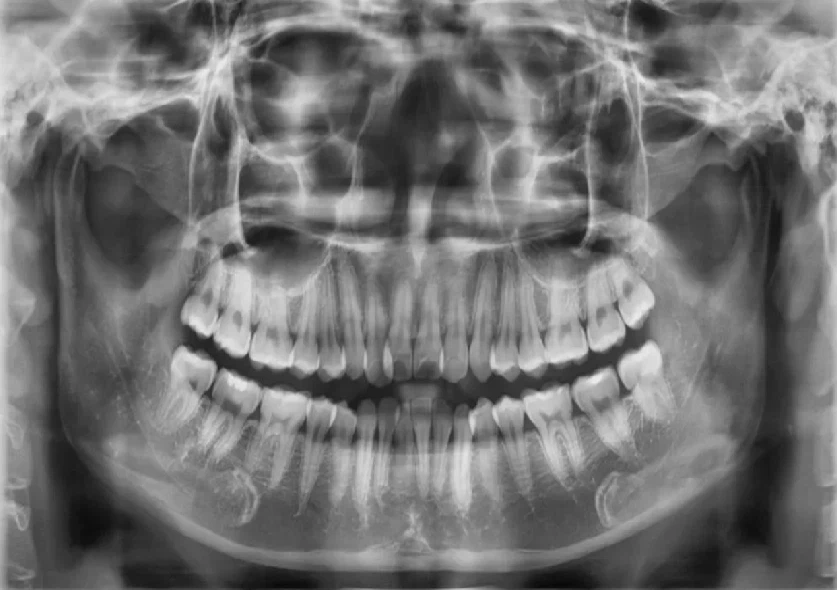

Bước 1: Thăm khám và tư vấn trực tiếp với bác sĩ chuyên cấy Implant

Bệnh nhân hỏng răng/mất răng khi có nhu cầu tìm lại hàm răng chắc khỏe bằng phương pháp cấy implant toàn hàm all on sẽ được thăm khám cùng bác sĩ một cách chi tiết, tỉ mỉ sau đó chụp phim CT ConeBeam. Khi có phim chụp X-quang, bác sĩ sẽ đánh giá mật độ xương hàm và lựa chọn số lượng trụ Implant phù hợp với tình trạng của bệnh nhân.

Kết quả chụp CT ConeBeam

Nếu bệnh nhân đáp ứng đầy đủ điều kiện để làm răng Implant all on và đồng ý với phương án, chi phí dựa trên sự tư vấn của bác sĩ thì ngay sau đó sẽ được đặt lịch hẹn cụ thể ngày đến nha khoa cấy implant.